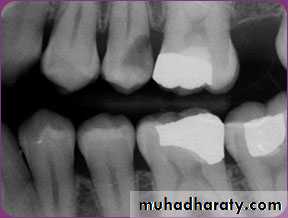

Bitewing radiograph. This radiograph shows (1) large occlusal caries, (2) radiolucent lines or mach band effect (an optical illusion caused by overlapped enamel), (3) interproximal caries, and

(4) cervical burnout